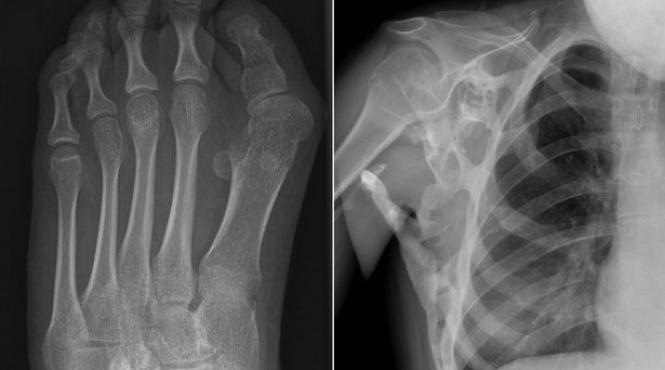

Boală NEMILOASĂ! În ce se transformă, treptat, o adolescentă (VIDEO)